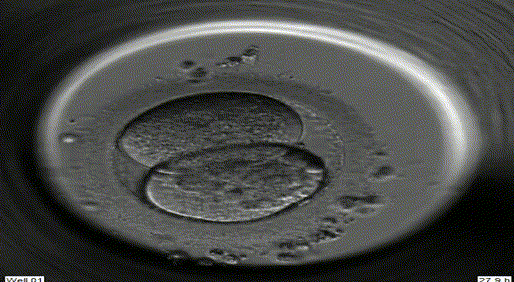

5体外受精

取卵后4-5小时将处理后的精子与卵子放在同一个培养皿中,共同培养18小时后,可在显微镜下观察受精情况。若精子质量太差,无法自然受精,则必需以单精子显微注射ICSI强迫受精。